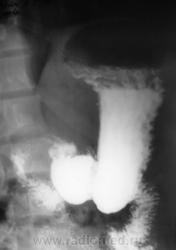

Примерно так....

...и другой пример, на "рельефе"...см. просто снимок и схему по снимку....